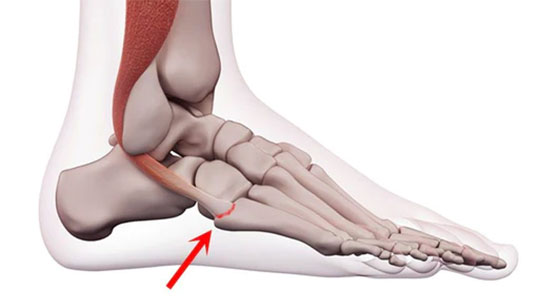

Peroneal Tendons run behind your outer ankle bone and link the bones in your foot’s arch to your lower leg muscles. They help you balance by stabilizing your arch when you walk and allow you to move your ankle. Peroneal Tendonitis occurs when your Peroneal Tendons are injured, stretched out, or become loose when you sprain or roll your ankle. A Peroneal Tear occurs when the tendon breaks or rips from an injury.

The tearing of your Peroneal Tendon can happen over time, especially if you’re prone to ANKLE SPRAINS. The Ankle Sprains loosen and stretch out the Peroneal Tendons which then become weak and frayed over time causing small tears and gaps in your tendon. Over-use (such as excessive running on uneven ground) can also cause peroneal tendonitis